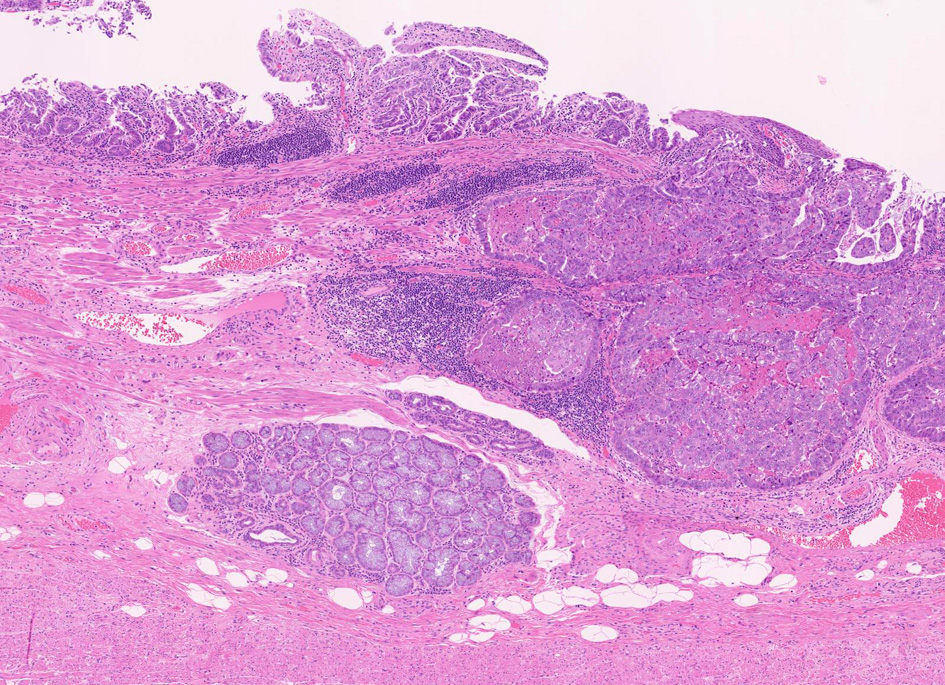

Fig.1 Barrett食道 腺癌Fig.2 EGP

1. 固有食道腺と導管が円柱上皮部位に存在する確定診断

2. 円柱上皮下の粘膜筋板二重化:かなり確実な所見,8割はあたり

EGPは常に扁平上皮から誘導されてできる腺で, その存在は必ず一度は粘膜内に扁平上皮があったという印であり食道固有の構造である。

扁平上皮島連続切片の観察では,すべての扁平上皮島は固有食道腺と導管を介して結合している

固有食道腺の開口部は必ず扁平上皮で囲まれており, 食道腺の上皮が進展しBarrett上皮ができるとする由来説は誤りである。